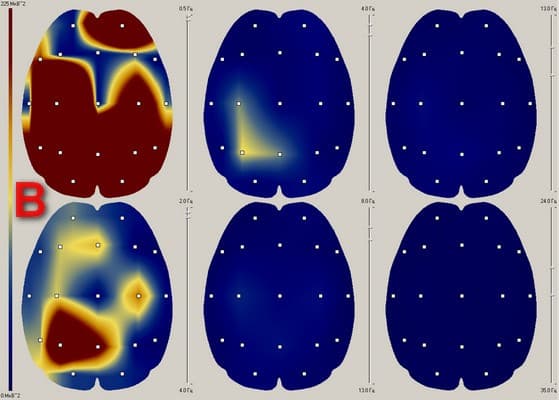

We present the examination results of one of the test subjects below:

Fig. 1. EEG spectral power distribution (mobile phone and Aires Shield located on the left ear):

Figure 1 shows that after a five-minute mobile phone conversation the test subject experienced a disruption of the rhythmic pattern of the baseline EEG and an asymmetric rhythm distribution.

In the area of the mobile phone, the asymmetry of delta activity increased by 37%.

The asymmetry caused by the mobile phone was completely leveled out in the presence of the Aires Shield electromagnetic anomaly neutralizer.

These experiments demonstrate that EMR from a mobile phone causes local changes in the EEG, disrupts the pattern of intercenter links, and leads to a disruption of the central nervous system, which can become the cause of a multitude of diseases of the central nervous system and internal organs.

The coherent transformation of the mobile phone’s EMR in the presence of the Aires Shield electromagnetic anomaly neutralizer prevents negative changes in the EEG from developing.

The EEG experiments confirm that the Aires Shield electromagnetic anomaly neutralizer reliably protects a person from the negative influence of a mobile phones EMR and maintains the regulatory functions of the central nervous system.